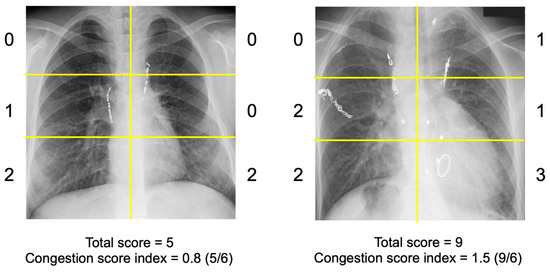

Background/Objectives: Remote dielectric sensing (ReDS) is a recently developed, noninvasive, electromagnetic energy-based technology designed to quantify pulmonary congestion without requiring expert techniques in adult patients with heart failure. However, its applicability in pediatric patients remains unknown. Methods: ReDS values and chest [...] Read more.

Background/Objectives: Remote dielectric sensing (ReDS) is a recently developed, noninvasive, electromagnetic energy-based technology designed to quantify pulmonary congestion without requiring expert techniques in adult patients with heart failure. However, its applicability in pediatric patients remains unknown. Methods: ReDS values and chest X-rays were simultaneously obtained from pediatric patients with a history of Fontan surgery at an outpatient clinic. The Congestion Severity Index (CSI) was calculated from chest X-rays to analyze its correlation with ReDS values. Results: A total of 21 pediatric patients (median age: 17 years; median height: 152.7 cm; median weight: 48.6 kg; 12 male patients) were included. ReDS values were successfully measured in all participants without any measurement failure. A mild correlation was observed between ReDS values and CSIs (r = 0.47, p = 0.030). In patients with ReDS values exceeding 35% (N = 11), a stronger correlation was noted between ReDS values and CSIs (r = 0.61, p = 0.046). In patients with ReDS values ≤ 35% (N = 10), ReDS values exhibited a wide distribution (25% to 35%) despite low CSI values. Conclusions: The ReDS system demonstrates potential as a feasible technology for the noninvasive quantification of pulmonary congestion in pediatric patients, irrespective of the severity of congestion. Notably, the ReDS system may have the potential to identify subclinical pulmonary congestion in pediatric patients with heart failure. Full article